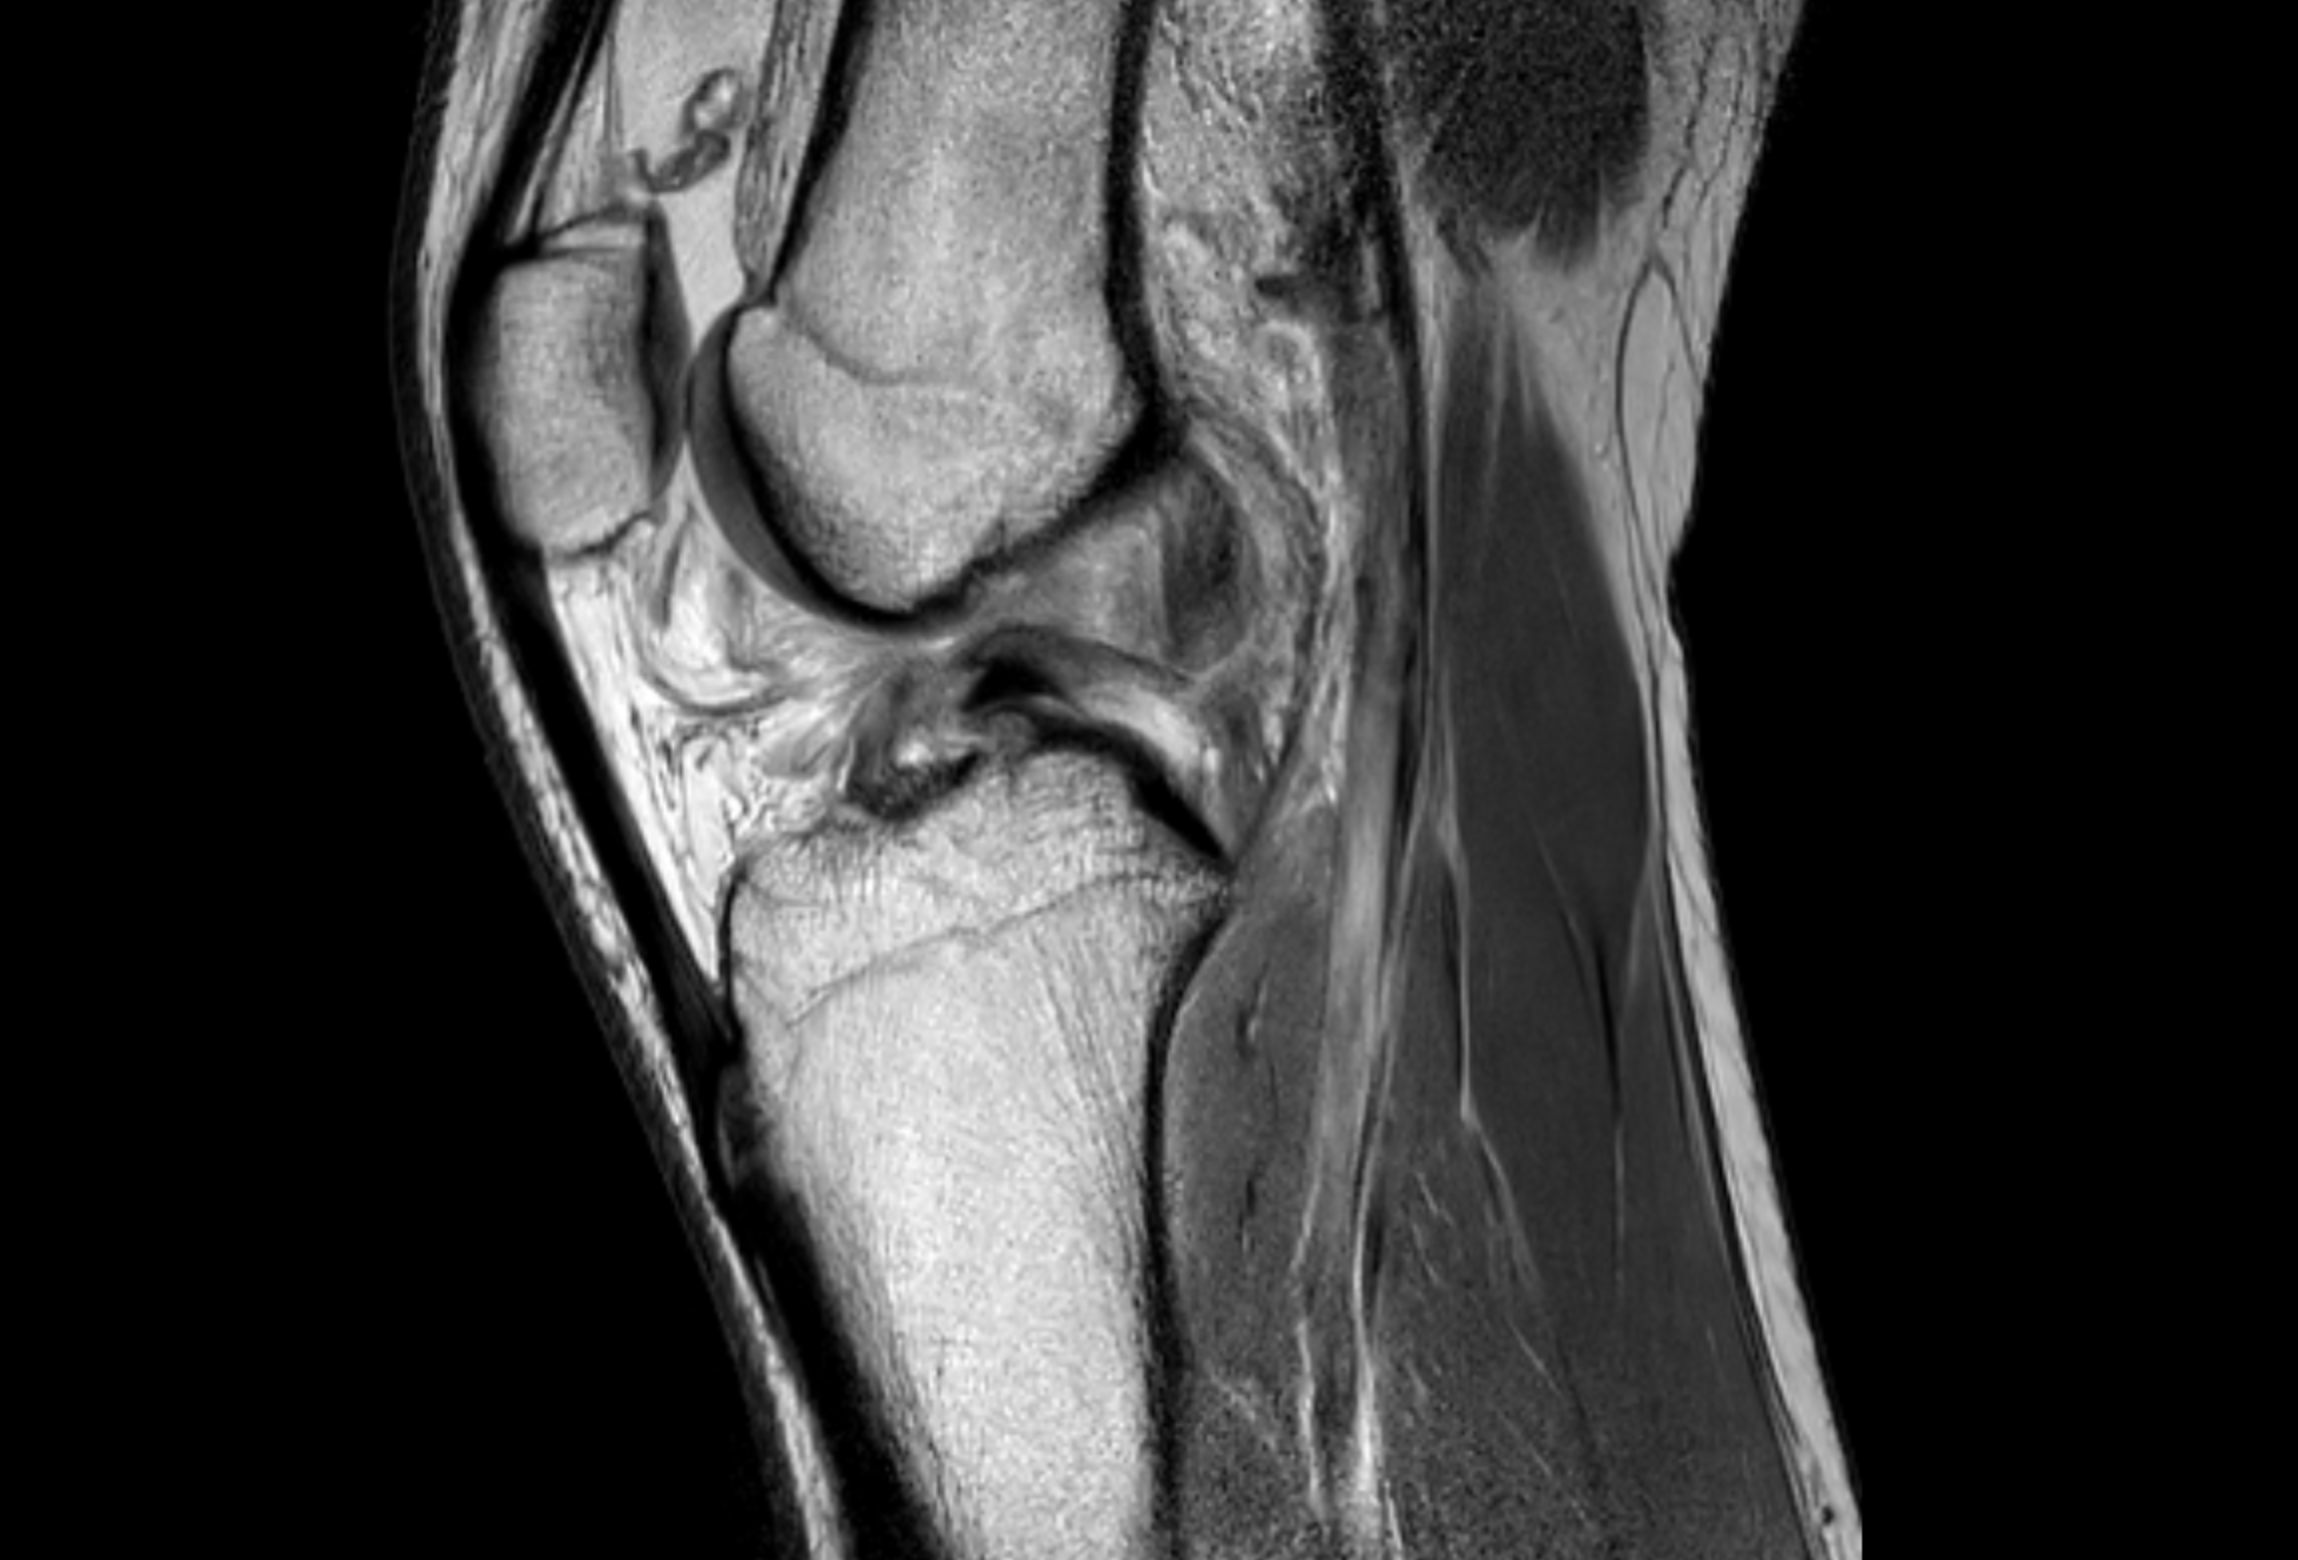

MRI is central to evaluating knee injuries because it reveals damage to joint structures, including ligaments, menisci and cartilage loss, providing a comprehensive whole-joint assessment. MRI can also detect abnormalities such as bone marrow lesions, effusion, synovitis and Baker cysts that cause symptoms and require management.

However, MRI interpretation varies across readers and practice settings and access to specialty-trained musculoskeletal radiologists is limited. By training AI models on a large multilingual dataset of knee MRIs paired with their original reports, this challenge aims to develop tools that can reliably identify abnormalities and support more consistent, timely care.